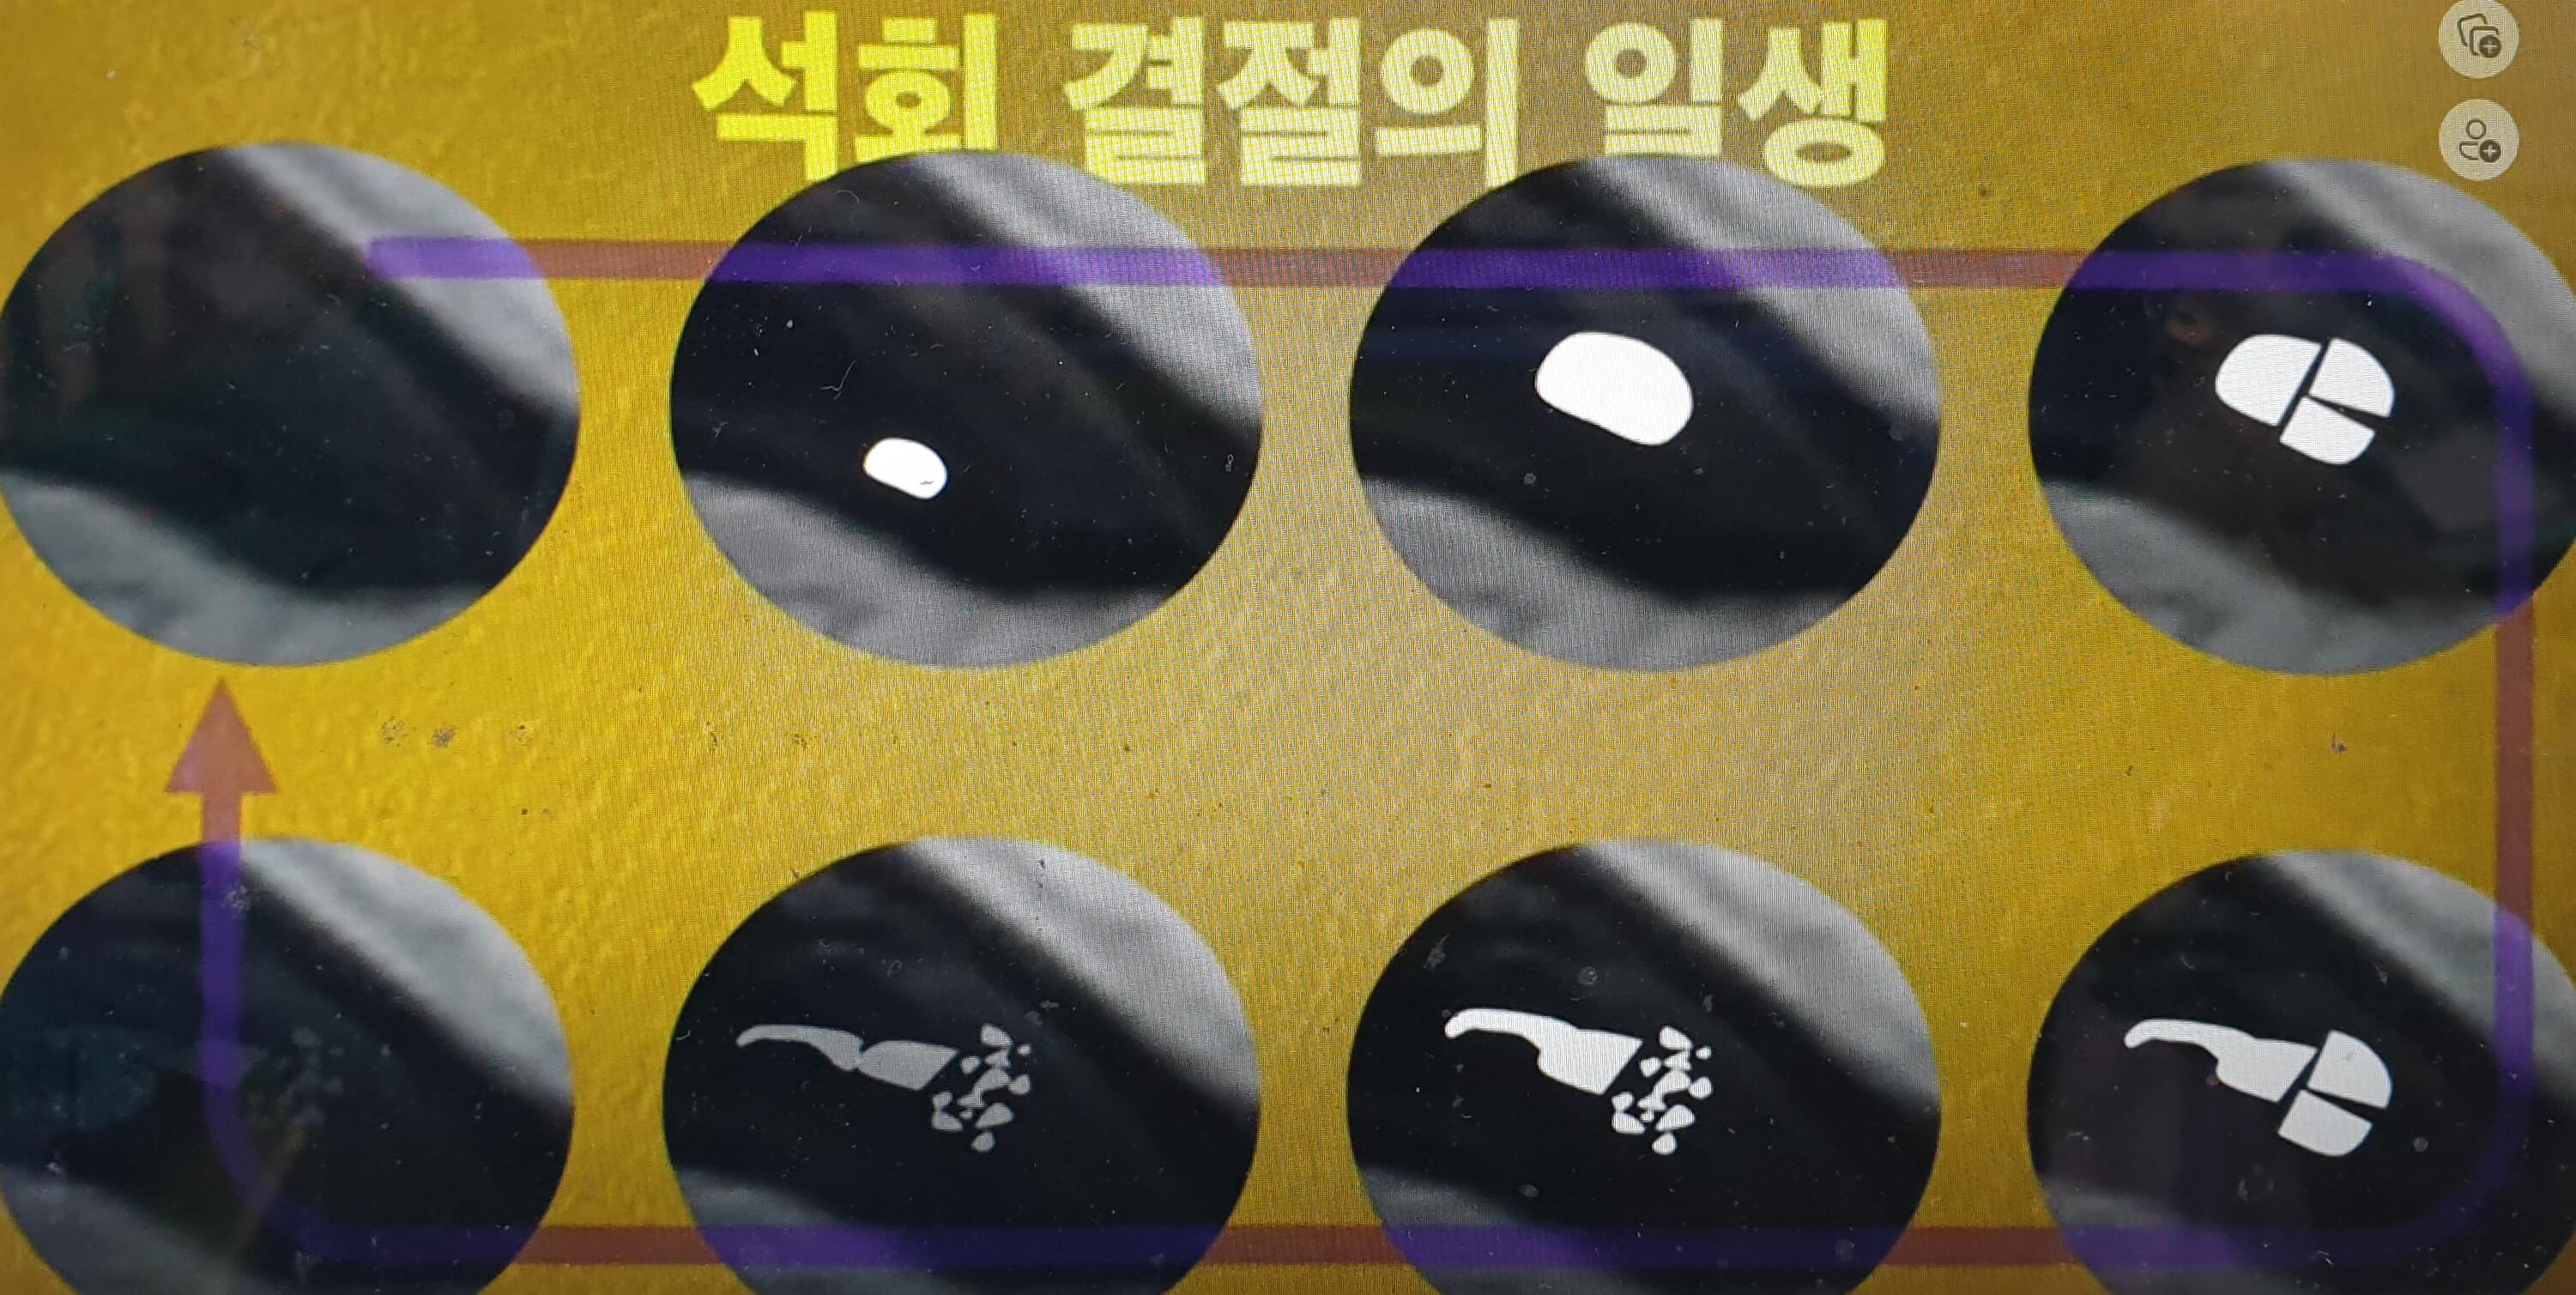

딱딱하게 뭉쳐져 있는 석회는 아프지 않지만 그것이 녹으면 아프게 되는 데 이를 이해하기 위해서는 석회 결정의 일생에 대해서 이해를 하셔야 합니다.

석회결절의 일생

위 사진의 맨 왼쪽처럼 처음에는 어깨 힘줄 부위에 아무것도 없는 깨끗한 상태이다가 어느 순간 석회 결절이 생기게 되고 그것이 점점 줄어 마지막에는 몸에 흡수되어 사라지게 됩니다. 더 자세한 석회결절의 변화과정을 알아보기 위해서 회전근개 힘줄을 중심으로 한 석회결절의 일생을 보겠습니다.

깨끗하던 회전근개 힘줄에 단단한 석회결절이 생기고 그 단단하던 석회결절이 시간이 지나며 차츰 녹기 시작하는데 녹아내리는 과정에서 크기도 부풀어지며 커지고 위치도 피부 쪽으로 이동하는 양상을 보이게 됩니다.(사진의 두 번째에서 세 번째 단계)

그러다가 조각이 나거나 (사진의 네 번째 단계) 터져 나오기도 하고(사진의 다섯 번째 단계) 아주 작은 조각들로 산산조각 나 부서져(사진의 여섯 번째 단계) 내리기도 합니다. 몇 년의 시간이 경과하면 차츰 녹아내리며 (사진의 일곱 번째 단계) 우리 몸으로 점점 흡수되어 예전에 석회가 없던 정상힘줄로 바뀌게 되는 것(사진의 여덟 번째 단계)입니다.

석회물질이 모두 다 흡수가 되면 대부분의 경우 특별한 손상이나 장애를 남기지 않고 예전과 같은 정상힘줄로 돌아가게 됩니다. 석회결절은 저절로 낫는 병이고 녹으면서 심하게 아픈 것 이외에는 크게 걱정할 것이 없다는 뜻입니다.